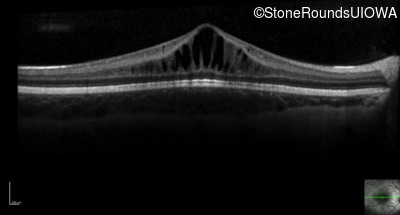

Optical Coherence Tomography - Right - 20/50 -1

Exemplar / OCT Stack